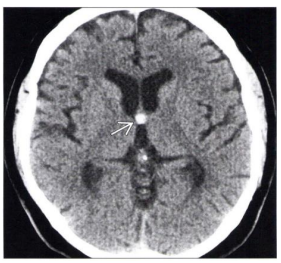

Tomografia do crânio sem contraste em corte axial ao nível do forame de Monro demonstra a imagem apontada pela seta na figura abaixo. O diagnóstico

CORRETO

é:

Cisto coloide.

Meningioma calcificado.

Astrocitoma de células gigantes.

Sangramento no interior do cavo do septo pelúcido.